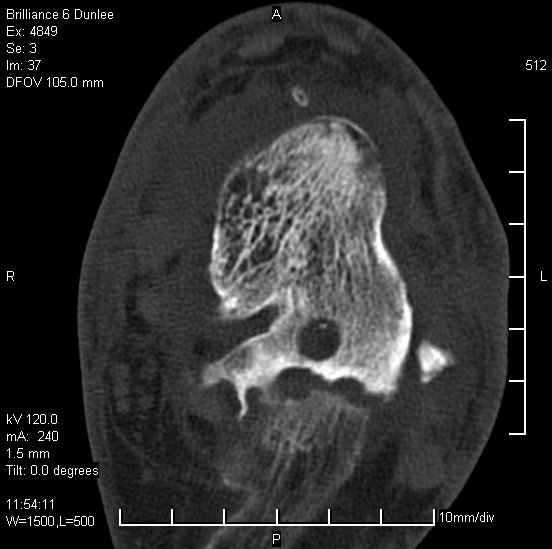

На лечении находится пациент 35 лет. Травма в сентябре 2008 г.- открытый вывих таранной кости

В день травмы ПХО, вправление вывиха, трансартикулярная фиксация. Рана зажила первично. С января нагрузка на конечность. С конца апреля- болевой синдром. На рентгенограммах и КТ признаки ас. некроза таранной кости, артроз подтаранного и голеностопного суставов.

У больного тотальный ас. некрох блока таранной кости, заинтересованы голеностопный и подтараный суставы. Эндопротезирование маловероятно на некротизированную кость. Изолированный подтаранный артродез таран не спасет.При артродезе всю некротизированную кость придется убрать.А далее замещение либо за счет большеберцовой кости, или удлинение на регенерате.